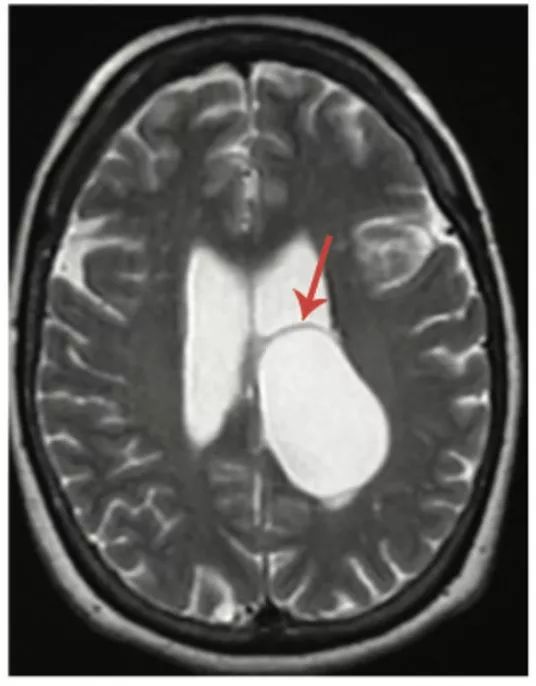

图10 胶样囊肿

轴位T2WI(A)和T1WI(B)显示第三脑室入口水平一个圆形边界清晰的囊肿(箭头),表现为典型的T2低信号和T1高信号。